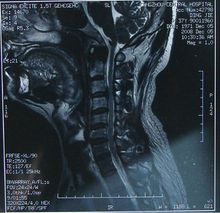

常規X線平片,主要是側位片上可清晰地顯示頸椎椎管矢狀徑。凡在標準投照距離180cm攝出的平片上矢狀徑小於12mm時,即具有診斷價值;12~14mm時有診斷參考意義;而在10mm以下時完全可以確診。此外亦可依據椎體與椎管的矢狀徑比值進行判斷,小於1∶0.75即屬異常,小於1∶0.6時具有診斷意義,比值在1∶0.5以下時完全可以確診。MRI檢查

可清晰地顯示椎管矢狀徑的大小、形態及其與脊髓受壓的關係。CT檢查主要顯示骨組織,而MRI檢查則對軟組織顯像較為清晰,因此二者結合起來最為理想,不僅有利於診斷,更有利於對椎管內組織狀態的判定,以決定治療方案及術式的選擇。除外診斷